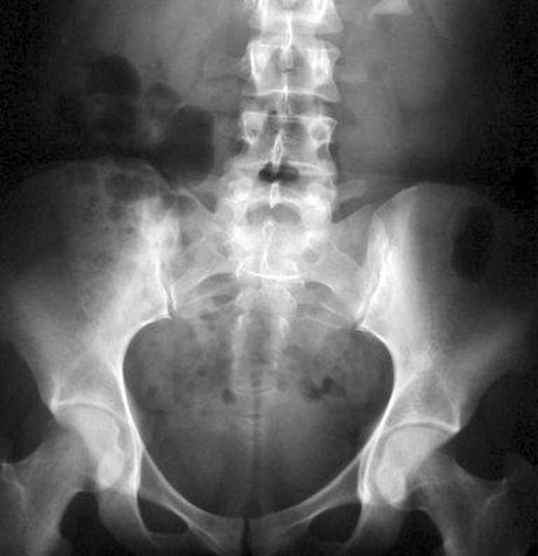

Запитання 23

НЕОПЕРОВАНИЙ ПЕРЕЛОМ ЦІЄЇ КІСТКИ І В ЦЬОМУ МІСЦІ ПРИЗВЕДЕ ДО СМЕРТІ В СЕРЕДНЬОМУ ЧЕРЕЗ КІЛЬКА РОКІВ. А ЦІ РОКИ ПЕРЕТВОРЯТЬСЯ НА СИДЯЧІ АБО ЛЕЖАЧІ МУКИ. ЯКОЇ КІСТКИ І ЯКОЇ ЇЇ ЧАСТИНИ?

варіанти відповідей

HUMERUS, ХІРУРГІЧНА ШИЙКА

ВЕРХНЬОГО ДІАФІЗА

FEMUR, ШИЙКА

ULNA, ШИЙКА

ПРОКСИМАЛЬНОГО ЕПІФІЗА

ДИСТАЛЬНОГО ЕПІФІЗА

HUMERUS, ШИЙКА

RADIUS, ШИЙКА

ДЕ ВИ БАЧИТЕ ЕЛЕМЕНТ КІСТКИ, ЗНАННЯ ЯКОГО НЕОБХІДНЕ В АКУШЕРСТВІ ДЛЯ ВИМІРЮВАННЯ РОЗМІРІВ ВЕЛИКОГО ТАЗУ? (ВЕРТЛЮГОВА ДИСТАНЦІЯ).